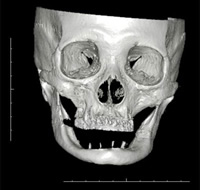

ですので私が治療の際に、「重要なのは噛み合わせ(咬み合わせ)なんですよ」というお話を頭蓋骨の模型などでご説明させて頂きますと、ほとんどの方が「先生、まさにおっしゃるとおりです」と本当にストレートにご理解くださいます。

歯の噛み合わせ(咬み合わせ)というのは、実は顎の状態から考えなくてはなりません。

下顎というのは、頭蓋骨に対して固定されることなくぶら下がっているものです。

下アゴは体の中で左右に渡ってぶら下がっている唯一の器官です。

つまりここがおかしいと全身のバランスを崩してしまう、ということが起こります。